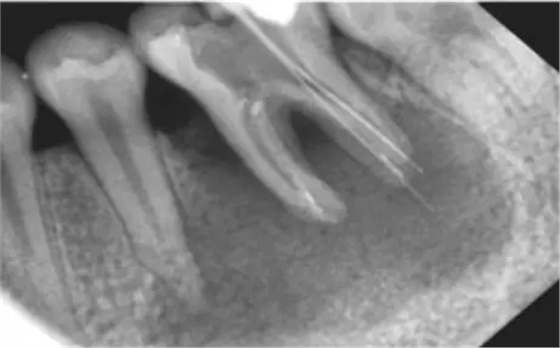

看下圖X光片是不是覺得欠充了呢?

其實(shí):X光片確定長(zhǎng)度經(jīng)常性引起超充?

X線片法缺陷 1)三維結(jié)構(gòu)投射在二維平面上,因投射角度不一樣,數(shù)據(jù)容易出錯(cuò)。 2)根尖孔不能體現(xiàn)在牙片上,而80%以上的根尖孔都不在牙齒根尖而是在側(cè)邊。 根尖開口在側(cè)邊時(shí),X線片投射引起長(zhǎng)度偏差錯(cuò)誤。 根尖開口距離牙齒根尖距離越大,誤差越大,會(huì)引起嚴(yán)重超充。 既然手感法和X光照片法都有明顯的缺陷,那么我們應(yīng)該如何去確定準(zhǔn)確的工作長(zhǎng)度?其實(shí)我們只要去接受現(xiàn)代根管治療的理念,使用根管長(zhǎng)度測(cè)定儀去測(cè)定就可以。根管長(zhǎng)度測(cè)定儀采用是電測(cè)法,是目前臨床最常見的方法,是根管治療的必備一起。測(cè)量時(shí)一個(gè)電極(唇鉤)掛于口角處,另一電極與根管銼(一般用15號(hào)k銼)相連,銼桿上的橡皮片與參照點(diǎn)接觸,當(dāng)銼尖達(dá)到根管最狹窄處時(shí),即可測(cè)出根管工作長(zhǎng)度。在剛開始使用根測(cè)儀時(shí),每位醫(yī)生都會(huì)有的點(diǎn)不習(xí)慣,覺得麻煩,但是習(xí)慣后就離不開根測(cè)儀了。 獲得準(zhǔn)確的工作長(zhǎng)度,你需要做的僅僅是改變,去使用根測(cè)儀去測(cè)量根管長(zhǎng)度。 來源于宇森醫(yī)療